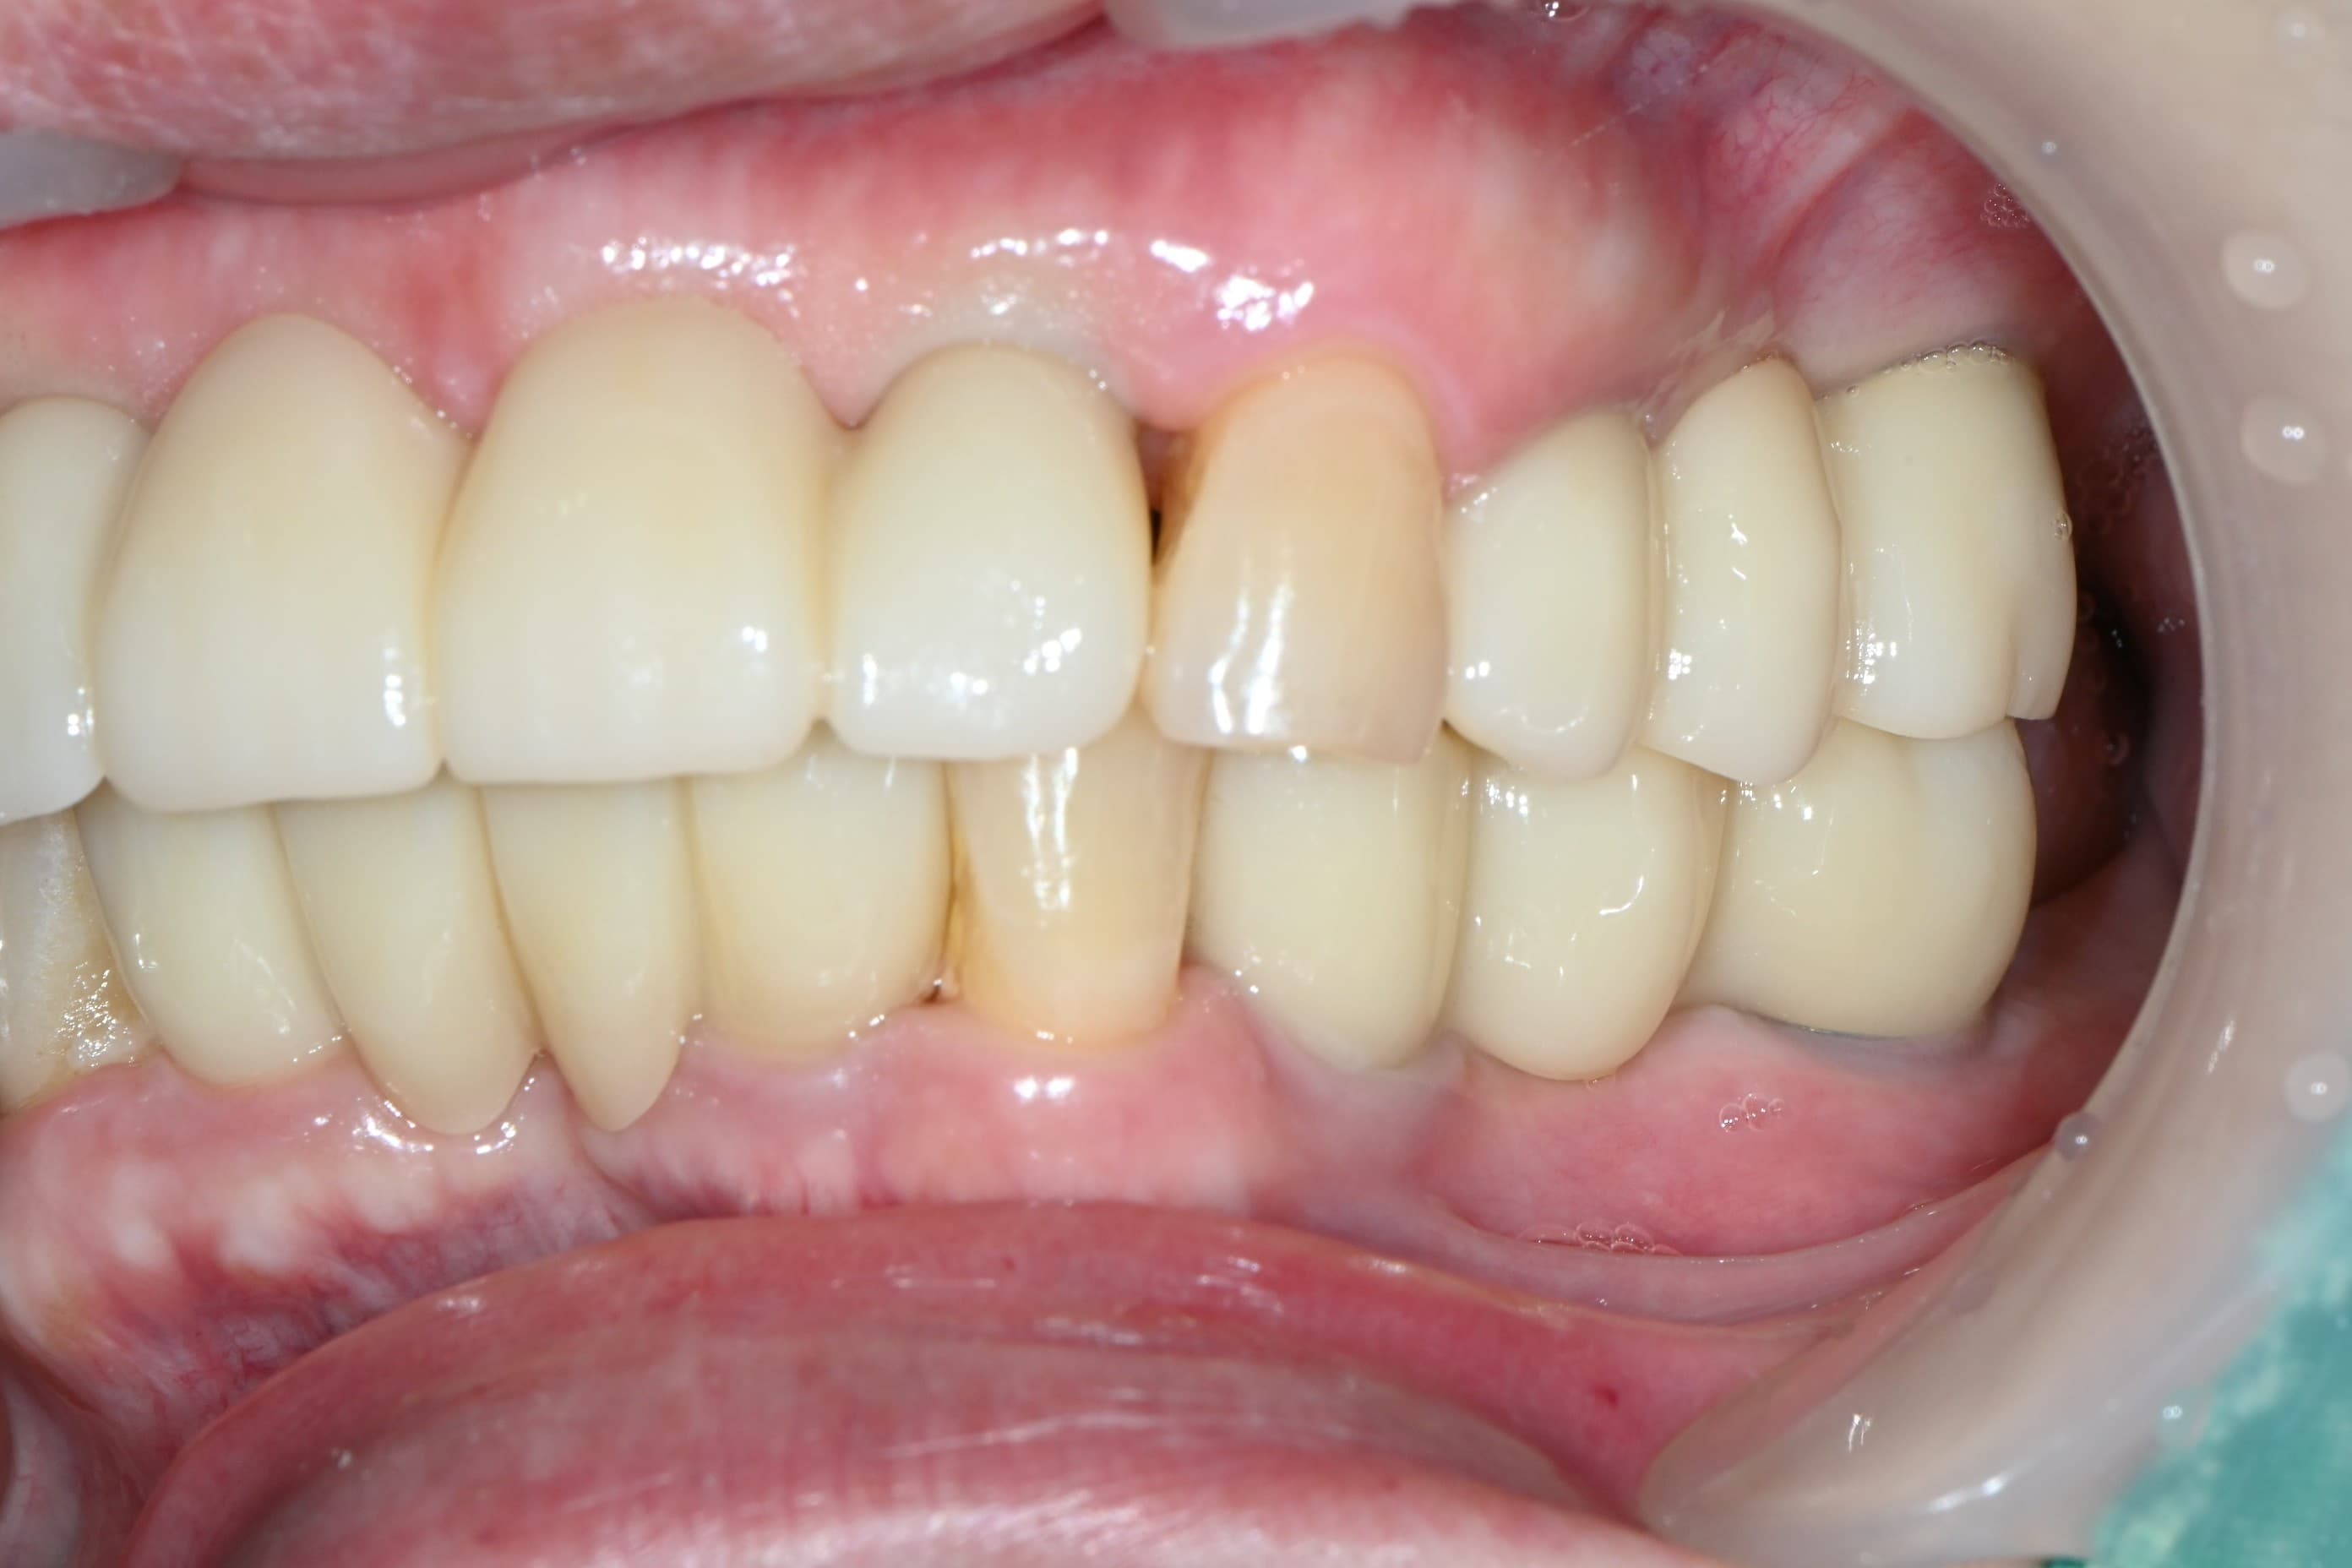

다수 임플란트 · 실제사진 · 지●● · 남성

임플란트 보철 · 실제사진 · 지●● · 남성

임플란트 · 실제사진 · 이●● · 여성